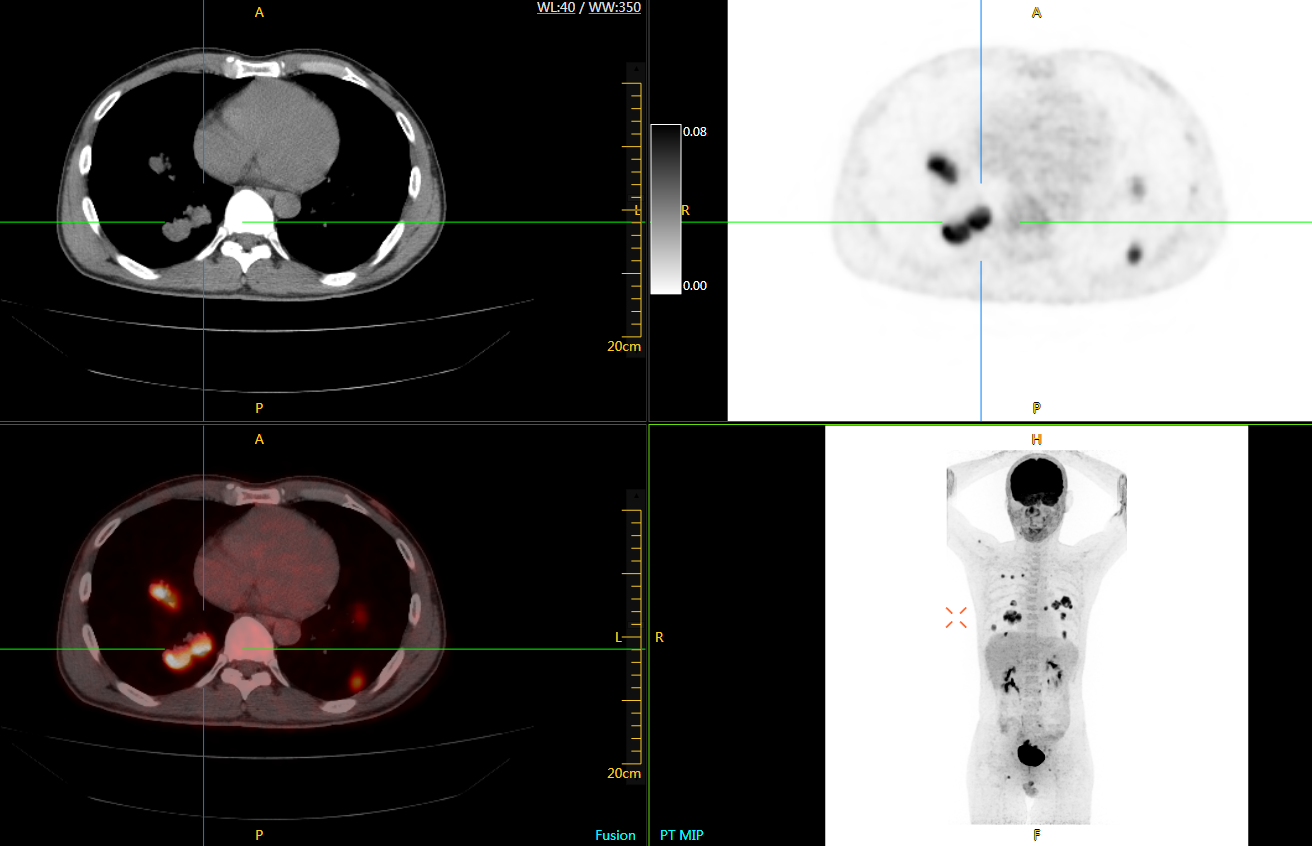

肺癌轉(zhuǎn)移及復(fù)發(fā)

患者男性,66歲,七年前發(fā)現(xiàn)右肺肺癌,其間手術(shù)兩次,共切除兩個(gè)肺葉,復(fù)查;

診斷意見,回腸轉(zhuǎn)移,右肺殘留部復(fù)發(fā)